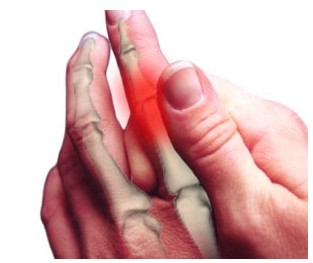

- 설명: 주로 손가락의 가운데 마디 관절이나 손목 관절, 발가락 관절 등 작은 관절에서 통증이 시작됩니다. 통증은 한두 개의 관절에서 시작해 점차 여러 관절로 퍼져나가는 경향이 있습니다.

- 관절 부위의 부종 (붓기)

- 설명: 염증 반응으로 인해 통증이 있는 관절이 부어오릅니다. 관절 부위가 붉고 뜨거워지는 열감과 함께 나타나며, 만져보면 물이 찬 것처럼 말랑말랑한 느낌이 들 수 있습니다.